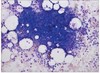

what is the name of this cell

megakaryocyte